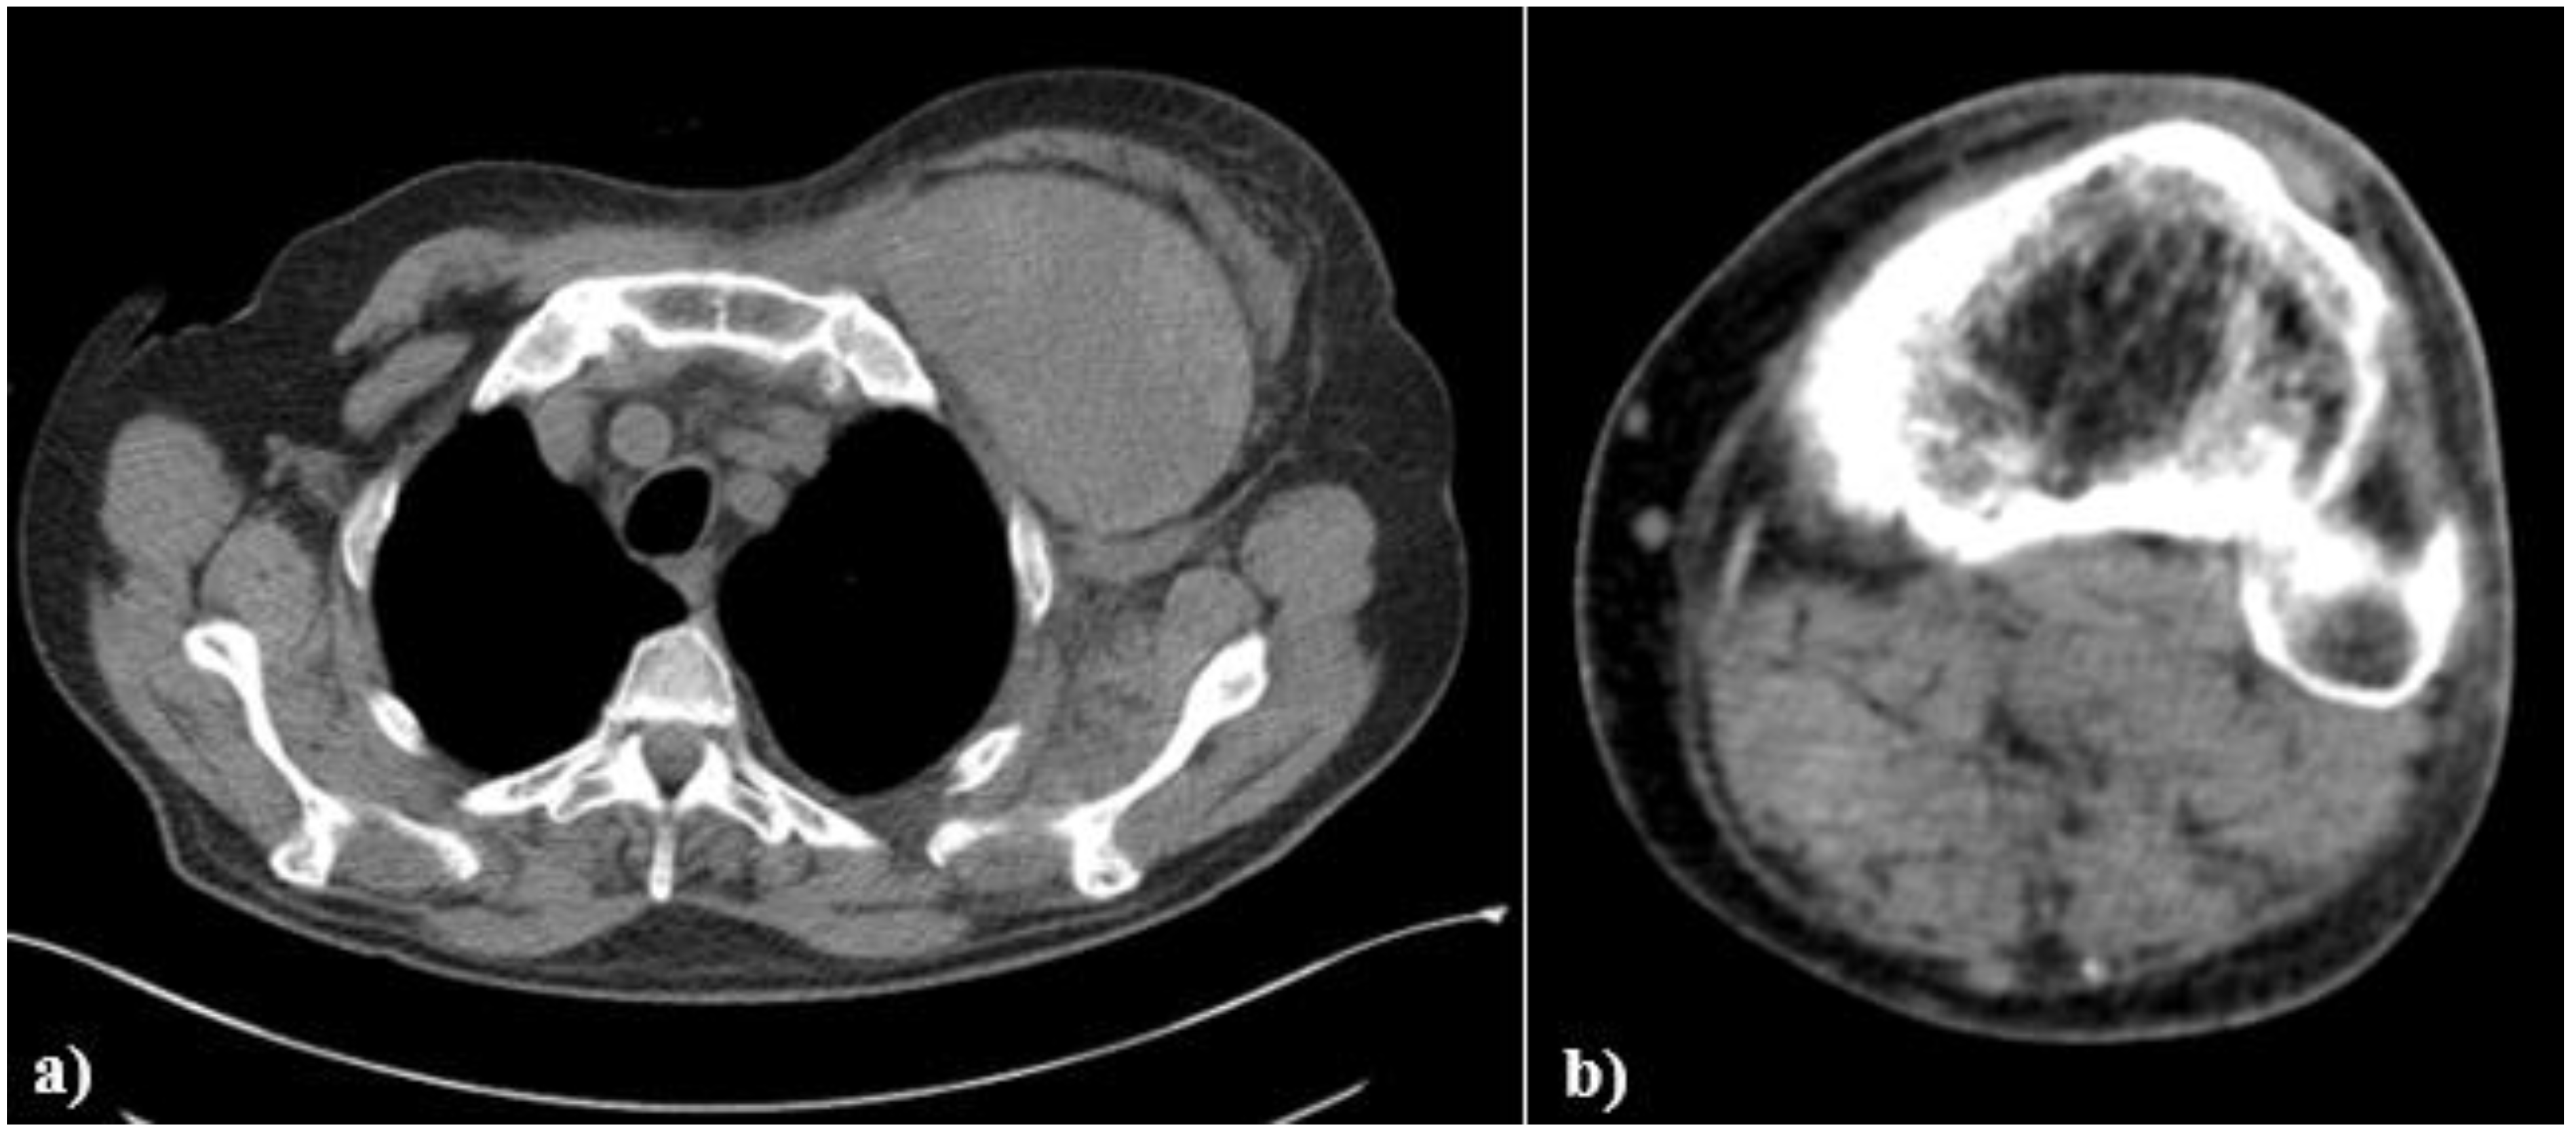

2. Case Presentation